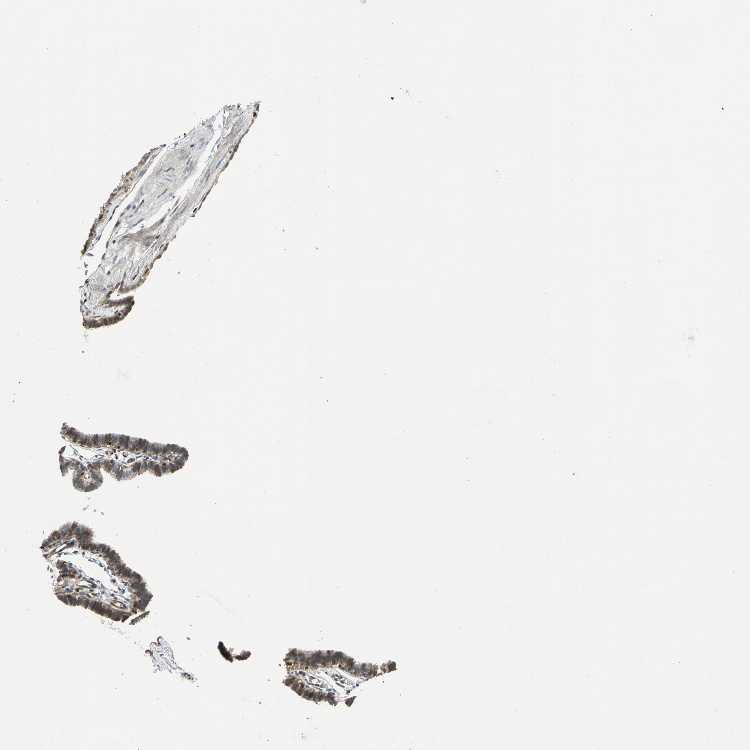

FALLOPIAN TUBE - Antibody stainingi

Antibody staining in the annotated cell types in the current human tissue is reported as not detected, low, medium, or high, based on conventional immunohistochemistry profiling in selected tissues. This score is based on the combination of the staining intensity and fraction of stained cells.

Each image is clickable and will lead to virtual microscopy that enables deeper exploration of all samples and also displays staining intensity scores, fraction scores and subcellular localization as well as patient and tissue information for each sample.

Antibody HPA029722Antibody HPA029723Antibody CAB005072

Ciliated cells (cell body) Not detected--

Ciliated cells (cilia axoneme) Not detected--

Ciliated cells (ciliary rootlets) Medium--

Ciliated cells (tip of cilia) Medium--

Glandular cells -LowMedium

Non-ciliated cells Medium--